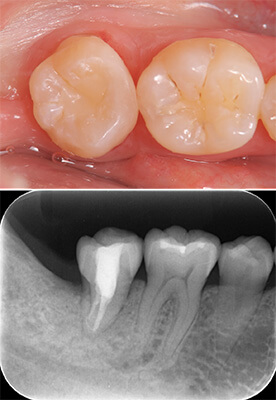

セラミックインレー

(1本6万円)

- Before

- After

技工士が歯の色に合わせて一つ一つ丁寧にセラミックインレーを製作します。

セラミックインレーの装着時には写真のようにラバーダムというゴムのシートを使うことにより接着力が増します。

接着力が増すと虫歯の再発率を減らすことにつながります。

治療のリスク

虫歯の範囲が大きいとクラウンによる治療の適応になります。

治療回数

2回